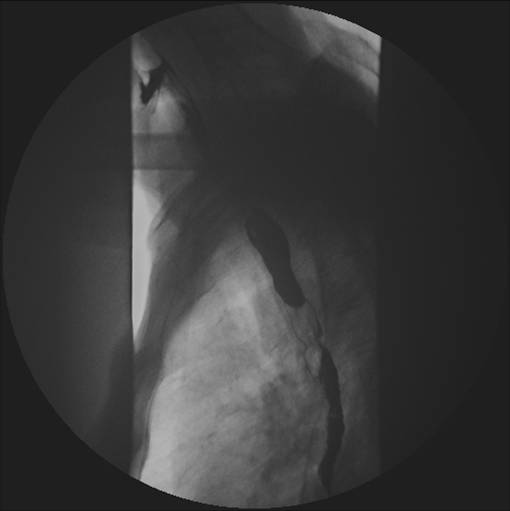

Kontrasten er på vej ned gennem diagfragma